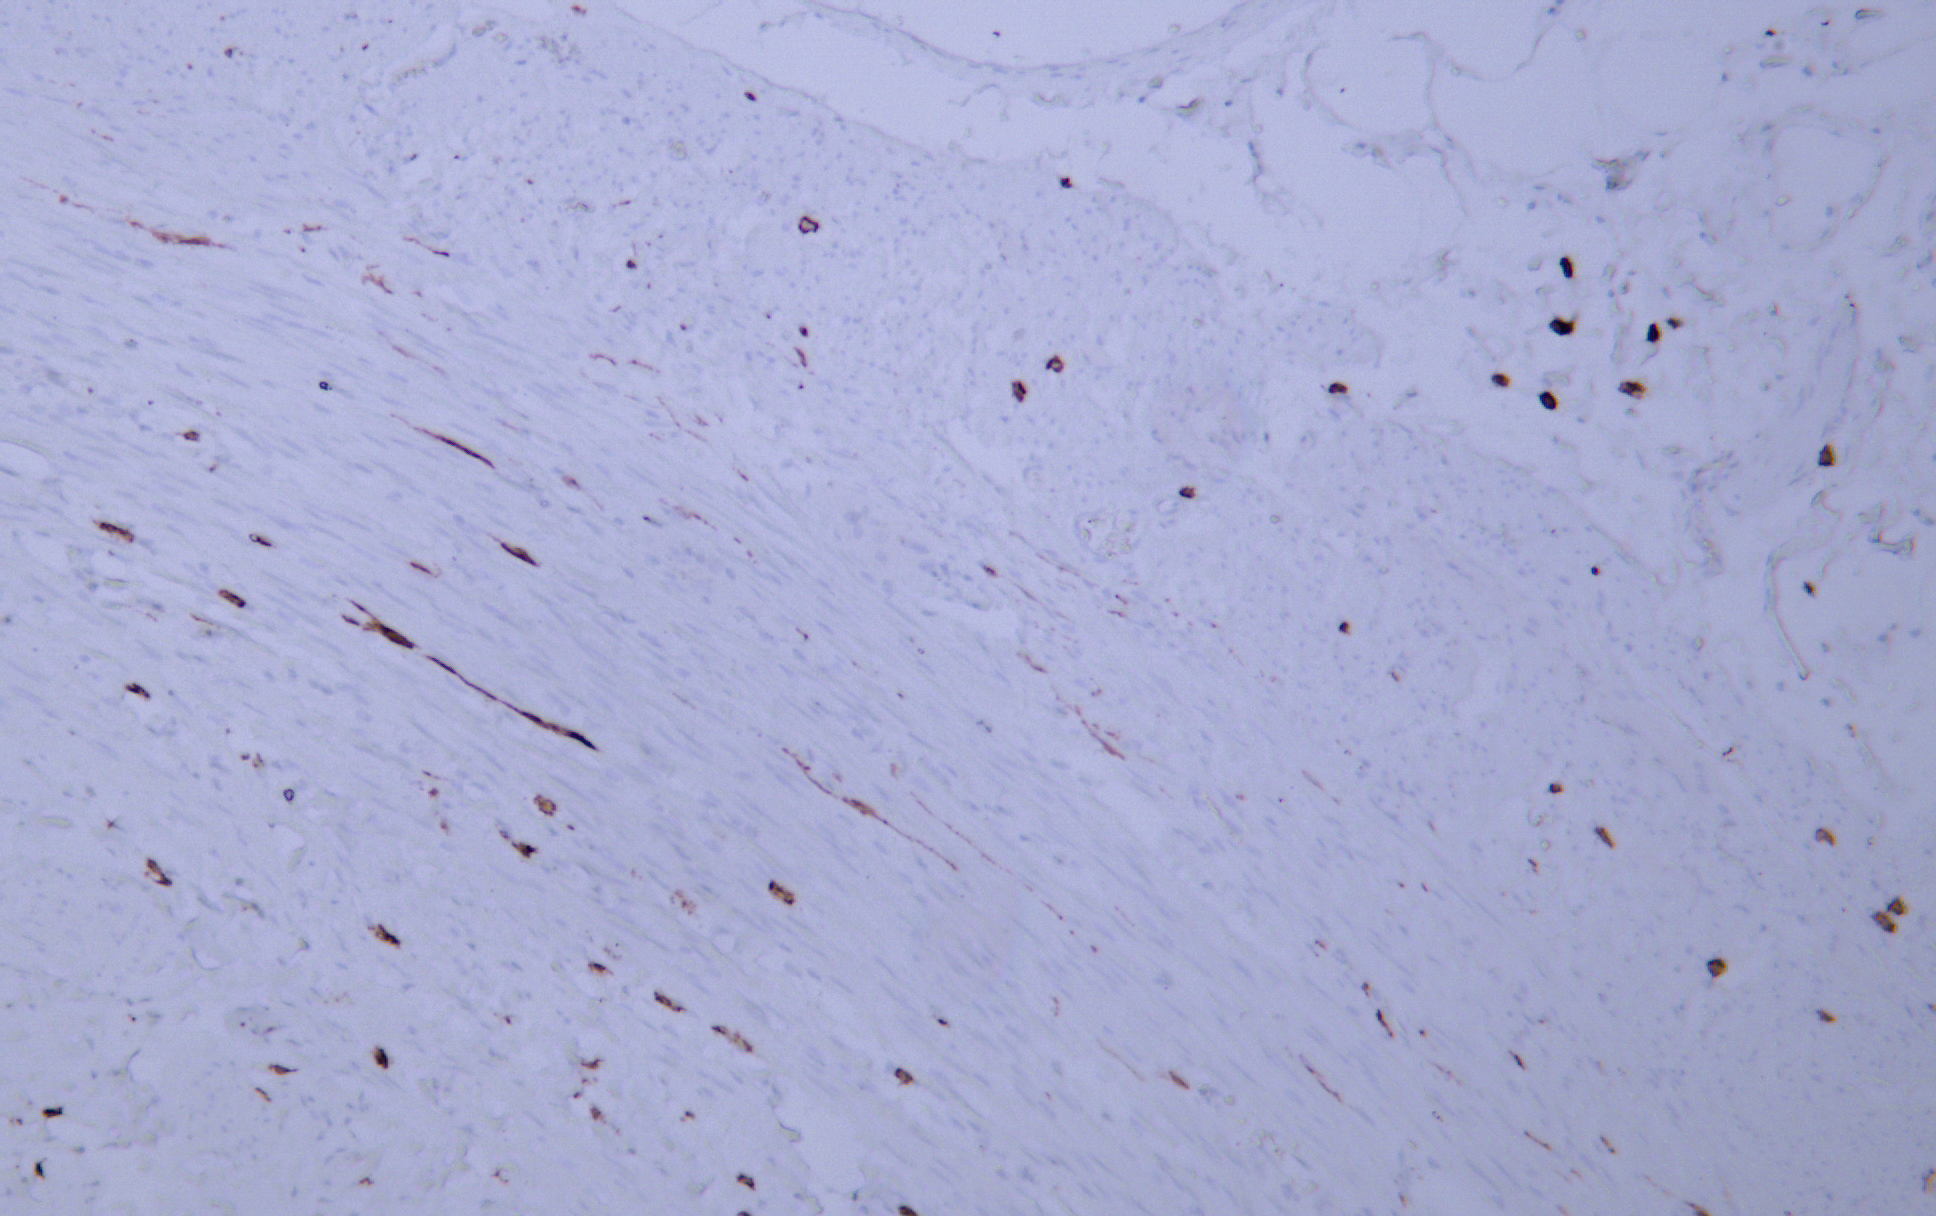

CD117 (C-kit) (AB1257) mouse mAb

Application:Immunohistochemistry (IHC)

CD117 is a cell membrane protein encoded by the c-kit proto-oncogene and is a type III transmembrane protein tyrosine kinase growth factor receptor. CD117 is expressed in mast cells, melanocytes and interstitial cells of Cajal. CD117 is positive in 80-100% of gastric stromal sarcoma (GIST) . CD117, as a specific marker for immunohistochemical examination of gastric stromal sarcoma (GIST) , can be used to clinically guide the personalized target drug (Gleevec) treatment of GIST patients. CD117 can also be used to identify mast cell tumors in lymphoma and as a marker for some testicular germ cell tumors.

Immunohistochemistry (IHC)

IHC, 1:50-1:200